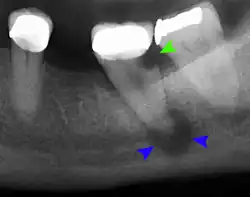

- Radiographs utilized to find dental caries and bone loss laterally or at the apex.

Decay (green) with apical abscess (blue) -